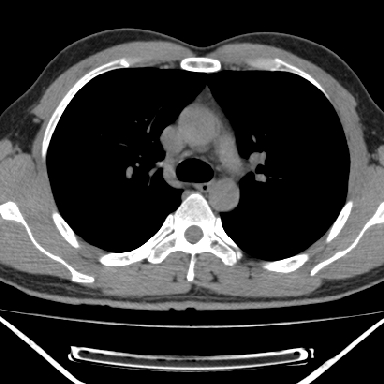

病灶与椎间孔间存在脂间隙,病灶较大,椎间无明显异常改变,与胸膜移行处可见尾状影,考虑胸膜肿瘤,以良性间皮瘤可能性大

支持, 椎体及附件未见破坏!

良性胸膜间皮瘤可能性大,神经源性肿瘤可能性小,因为没有见到有瘤体组织伸入神经孔内!

右上后纵隔脊柱旁见长椭圆形肿块,边界光整,与胸壁呈钝角。周围骨质未见异常。

考虑、1、后纵隔神经源性肿瘤;

2、不除外单发胸膜间皮瘤。